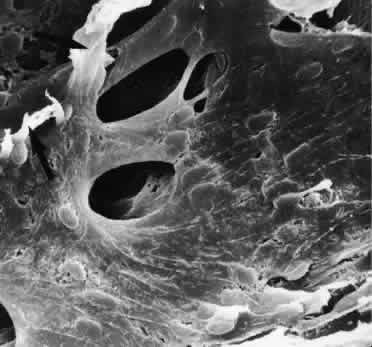

OUTFLOW CHANNELS OF SCHLEMM'S CANAL

After passing through the TM, aqueous humor enters Schlemm's canal and then the collector channels. Schlemm's canal is not a uniform vessel but is often divided into different parts by bridges or septa.79 The septa cross the lumen of the canal mostly in an oblique direction. They are often fixed to the outer wall of the canal at places where the collector channels begin. Thus the septa, which often form twisted or spiral bands, can be considered to be guiding structures for aqueous humor toward the openings of the collector channels (Figs. 24 and 25). Some bridges do not cross the entire lumen of the canal but remain part of the outer wall, adjacent to a collector channel entrance. The number and form of septa and bridges vary to large extent. There are also regional differences with regard to form, number, and development of these structures.

Fig. 24. A and B. Scanning electron micrographs of sagittal sections of the trabecular meshwork and Schlemm's canal of human eyes showing different types of septa and intracanalicular bridges (arrows; A, × 500; B, × 620).